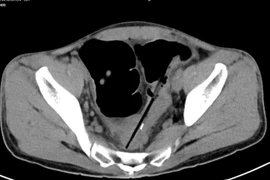

Cứu sống kịp thời cụ bà 72 tuổi thủng đại tràng sigma nguy kịch tại bệnh viện

Nhờ chẩn đoán nhanh và phẫu thuật cấp cứu, cụ bà 72 tuổi vượt qua nguy hiểm, giảm thiểu biến chứng nặng do thủng đại tràng sigma.